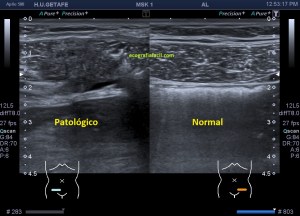

Durante la exploración de una eco de abdomen en el contexto de un paciente que acude por elevación de transaminasas observo una imagen heterogénea, irregular, con una pared marcadamente calcificada, bilobulada de gran tamaño que medí en dos partes ya que me pareció claramente que estaban diferenciadas.

Una de ellas, la primera, era mucho más hiperecogénica y más pequeña, su centro estaba mas calcificado, su sombra acústica posterior era mucho más acuciada y llamaba más la atención. Justo al lado, otra lesión de mayor tamaño, su calcificación era mucho más sutil y más periférica delimitando una LOE hipoecogénica de un tamaño muy importante, adyacente a la más pequeña, como he comentado previamente. Ambas sin señal Doppler.